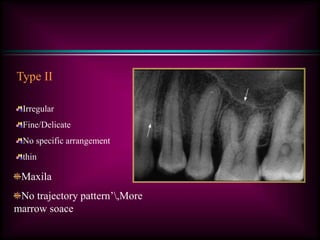

Type II

Irregular

Fine/Delicate

No specific arrangement

thin

Maxila

No trajectory pattern’,More

marrow soace